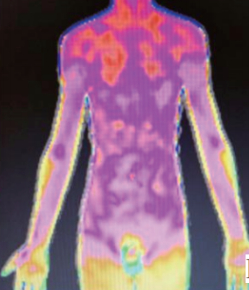

不同的中医证候分型在红外热成像仪上有明显差异,红外热成像技术进行体质测评,与现行的体质量表法评估相比,为中医临床辨证分型提供了直观的、可视化的证据。

特禀体质包含过敏体质,累及全身免疫系统,代谢紊乱,可见全身花斑样改变。

根据实验结果拟提取的红外热成像特征敏感区域如下:阴虚体质,面颊高温;气郁体质,额部睡眠线;阳虚体质,胃脘部低温区;痰湿体质,腹部低温;特禀体质,躯干花斑样改变等。